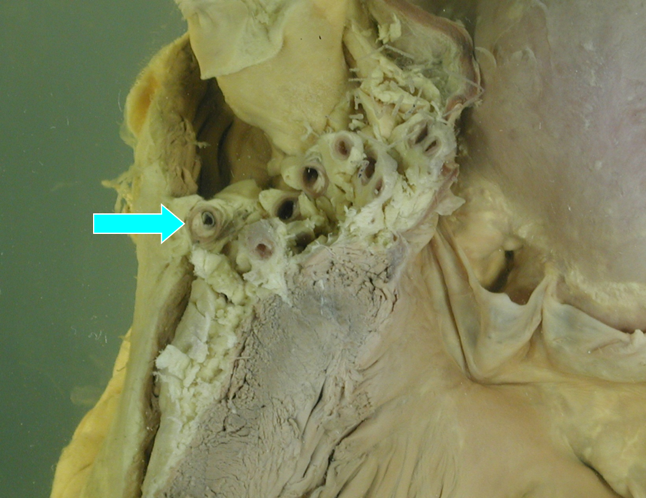

(5)动脉瘤形成:严重粥样斑块由于其底部中膜平滑肌萎缩变薄,弹性减弱,不能承受血流压力而向外局限性扩张,形成动脉瘤,动脉瘤破裂可致大出血。另外,血流可从粥瘤溃疡处侵入主动脉中膜,或中膜内血管破裂出血,均可造成中膜撕裂,形成夹层动脉瘤。

(图3-14)